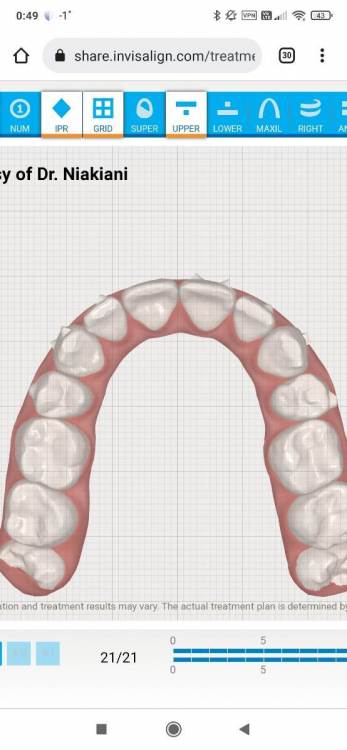

gomyranchik Опубликовано 31 декабря, 2021 Поделиться Опубликовано 31 декабря, 2021 Добрый день! 1) Могут ли элайнеры изменить наклон корней моляра? (на рентгеновском снимке видно, как корни одного из моляров сильно отклонены) 2) Стоит ли в моем случае вообще исправлять данный наклон? Насколько это критично, может ли быть негативное влияние в будущем, если оставить всё, как есть? Мне 33, живу с этим всю жизнь. Проходила лечение брекетами 11 лет назад, но мне тогда этот зуб не трогали. 3) Подскажите, пожалуйста, насколько реализуем данный план лечения с помощью инвизилайн (ссылка и доступ ниже)?https://share.invisalign.com/treatment-viewer/latest/index.html#/welcome?shareId=f24fef88-c45c-43f0-a76c-6c4690014908&shareThrough=PATIENT Пароль для входа: **** Заранее большое спасибо! Ссылка на комментарий

АнтонТЛТ Опубликовано 5 января, 2022 Поделиться Опубликовано 5 января, 2022 Задние бугры верхнего левого первого моляра находятся ниже уровня где они должны быть, это связано с выдвижением зуба из-за длительного наклона нижнего левого первого моляра. Так же этот верхний зуб находится в более нёбном положении относительно соседних зубов. Ссылка на комментарий

АнтонТЛТ Опубликовано 5 января, 2022 Поделиться Опубликовано 5 января, 2022 (изменено) Если провести воображаемую линию по режущим краям передних зубов и по щечным буграм жевательных зубов верхней челюсти то должна получиться элиптическая линия без ступенек, в Вашем случае не все зубы довернуть. Изменено 5 января, 2022 пользователем АнтонТЛТ 1 Ссылка на комментарий